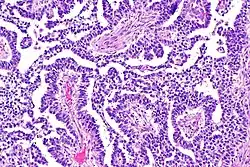

Teratomas

Teratoma are most common germ cell tumor of ovary. Teratomas can be divided into two types: mature teratoma (benign) and immature teratoma (malignant). Immature teratomas contain immature or embryonic tissue which significantly differentiates them from mature teratomas as they carry dermoid cysts.[5] It is commonly observed in 15 to 19-year-old women and rarely in women after menopause.[6] Immature teratomas are characterized with a diameter of 14–25 cm, encapsulated mass, cystic areas, and occasional appearance of hemorrhagic areas.[7] The stage of immature teratomas is determined depending on the amount of immature neuroepithelium tissue detected.[5]